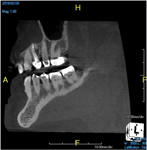

(10.) Tooth No. 31 in this 14-year-old patient does not exhibit caries. It is a “ghost tooth.” The lack of a periapical pathosis, the location of the tooth relative to the inferior alveolar nerve, and the development of tooth No. 32 are all visible in the CBCT image. These factors will aid the clinicians in developing a treatment plan to deal with this unusual internal resorption case.

Figure 10